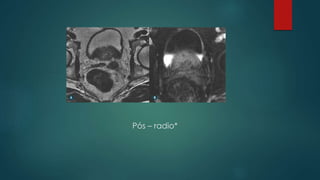

Pós – radio*